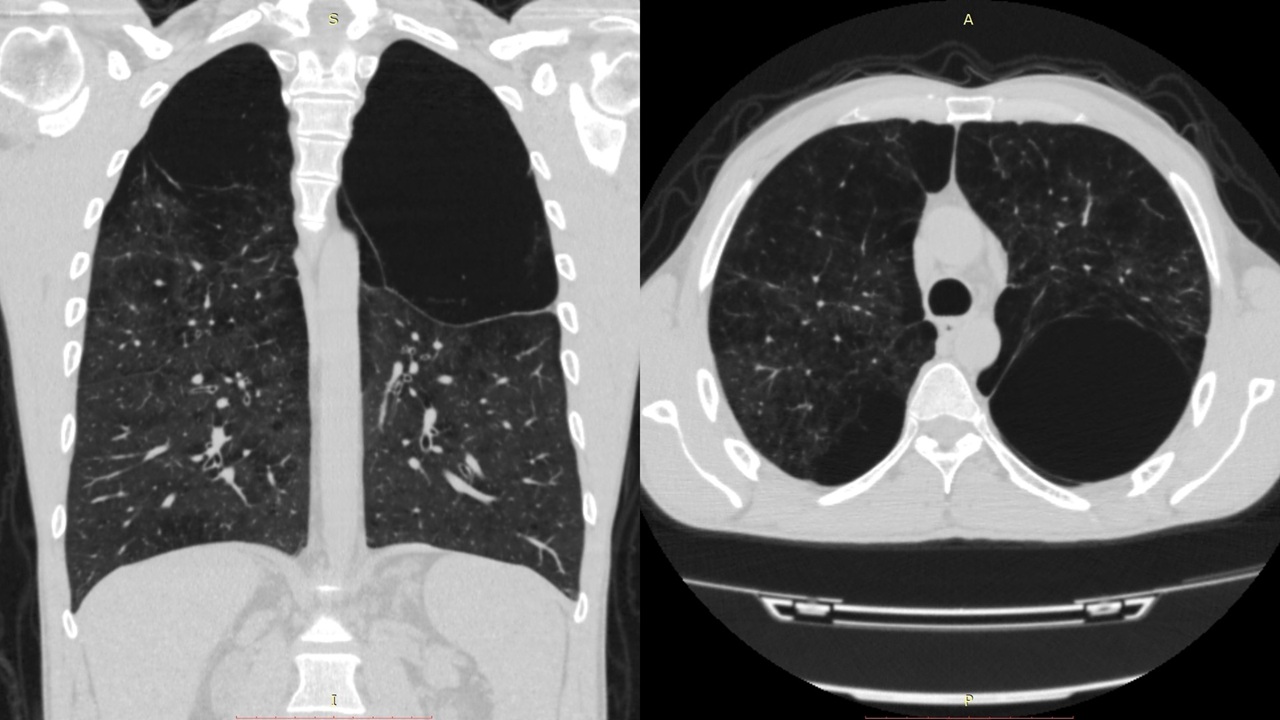

პაციენტი 42 წ მამაკაცი. აქტიური მწეველი. თავს ავად გრძნობს რამოდენიმე თვეა. ჩივილები: ძლიერი ქოშინი ფიზიკურ დატვირთვაზე, ჰაერის უკმარისობა, საერთო სისუსტე. გულმკერდის კტ კვლევით – ორივე ფილტვის ზედა წილებში გაიშვიათებული ფილტვის ქსოვილი, გიგანტური ბულები 10-14 სმ ზომის (16 იან 2020 წ). ბოდიპლეტიზმოგრაფიით – RV (Pleth) 3.90 ლ (Normal Range 1.14-2.49 ლ) (18 თებ 2020 წ). 2020 წლის 18 თებერვალს მარცხენა ფილტვის მოცულობის შემცირების მიზნით პაციენტს ჩაუტარდა რიგიდული ბრონქოსკოპია – სარქვლოვანი ბრონქობლოკაცია. ზოგადი გაუტკივარების ქვეშ ტრაქეაში შეყვანილი იყო Friedel-ის რიგიდული ბრონქოსკოპი. გამოყენებული იყო ტუბუსი N13. მარცხენა ზ/წ ბრონქის სანათურში მოთავსდა სარქვლოვანი ბრონქობლოკატორი N15. მანიპულაციიდან 3 თვის შემდეგ საკონტროლო გულმკერდის კტ კვლევით – მარცხენა ზედა წილში გიგანტური ბულა აღარ ფიქსირდება, ბოდიპლეტიზმოგრაფიით – RV (Pleth) 2.44 ლ (Normal Range 1.14-2.49 ლ) (25 მარ 2020 წ). გულმკერდის კტ კვლევით დადებითი დინამიკა შენარჩუნდა 9 და 12 თვის შემდეგ.